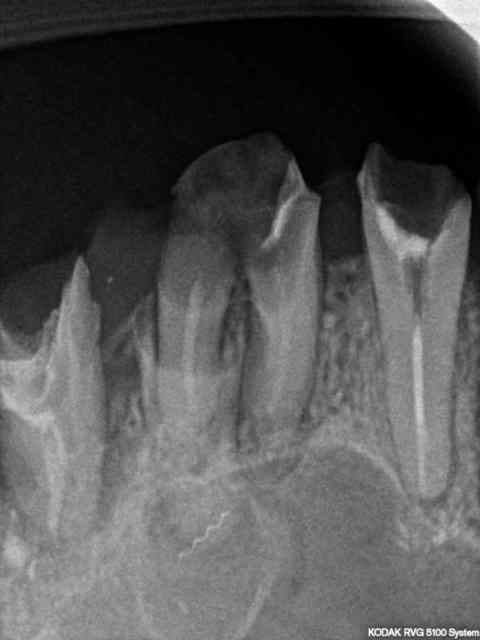

je voudrais votre avis sur cette 26 à extraire . Que pensez vous du fragment de lentulo cassé ? est-ce qu'il viendra facilement avec la racine ? palatine? doit - je déléguer à un stomato?

Je pense que le lentulo viendra sans problème car il me semble qu'il est au centre d'un kyste d'1cm de diamètre.

A confirmer avec une radio mieux centrée.

... il faut peut-être s'attendre à une CBS là; vas-y mollo lors du curetage du kyste.

Le lentulo lui, il viendra avec.